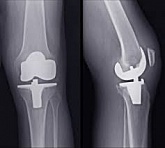

Endoprothetik des Kniegelenks

In den späten Stadien der Arthrose des Knies durch eine ausgeprägte Begrenzung der Bewegung begleitet, konstant starke Schmerzen, körperliche Unversehrtheit Verformung bis zur Genesung der einzige Weg ist der Ersatz des betroffenen Gelenks für eine künstliche - Endoprothetik.

Diese Methode ermöglicht es Ihnen, die richtige Form des Gliedes, eine vollständige Palette von Bewegung im Gelenke, zu entlasten ständige Schmerzen und Knirschen bei Bewegung und als Ergebnis wieder herzustellen, signifikant dem Patienten Lebensqualität zu verbessern.

Im Folgenden sind Röntgenaufnahmen und Fotografien, die die Strecke der Bewegung in der betroffenen Gelenke vor und nach der Operation veranschaulichen.